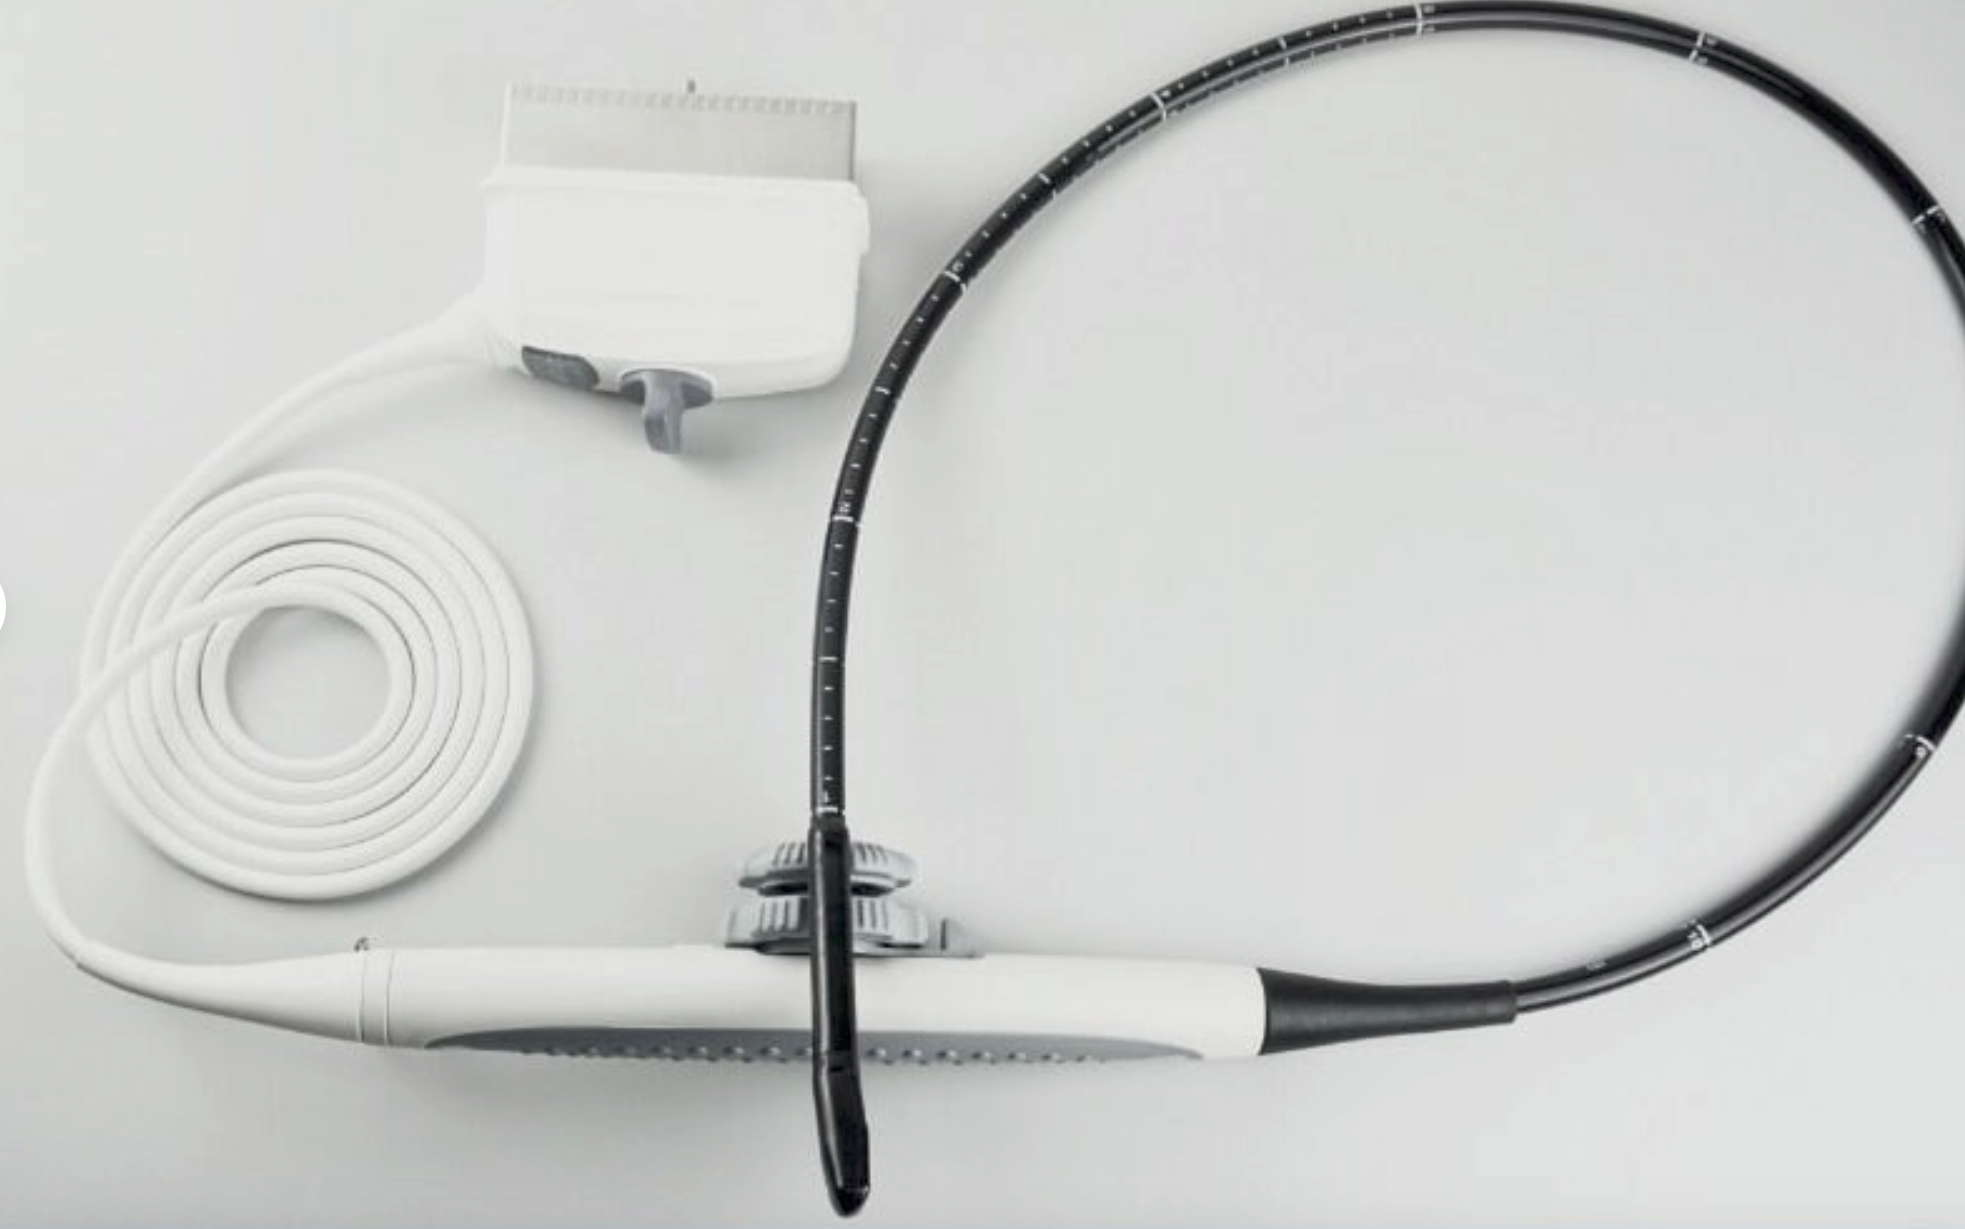

Genuine TOSHIBA PLT-1204BT Ultrasound probe transducer warranty 6 months

Sale price$ 2,787.30

Regular price$ 3,399.15

Save $ 611.85

DIAGNOSTIC ULTRASOUND MACHINES FOR SALE

Genuine TOSHIBA PLT-805AT ULTRASOUND PROBE transducer warranty 6 months DOM 2007

Sale price$ 2,787.30

Regular price$ 3,399.15

Save $ 305.85

DIAGNOSTIC ULTRASOUND MACHINES FOR SALE

Genuine TOSHIBA PLT-805AT ULTRASOUND PROBE transducer warranty 6 months DOM 2011

Sale price$ 1,393.30

Regular price$ 1,699.15

Genuine TOSHIBA PVM-651VT Endocavity ultrasound probe

Sale price$ 3,478.43

Regular price$ 4,241.99

Genuine TOSHIBA PVT-674BT Ultrasound probe transducer warranty 6 months-2007

Sale price$ 2,787.30

Regular price$ 3,399.15